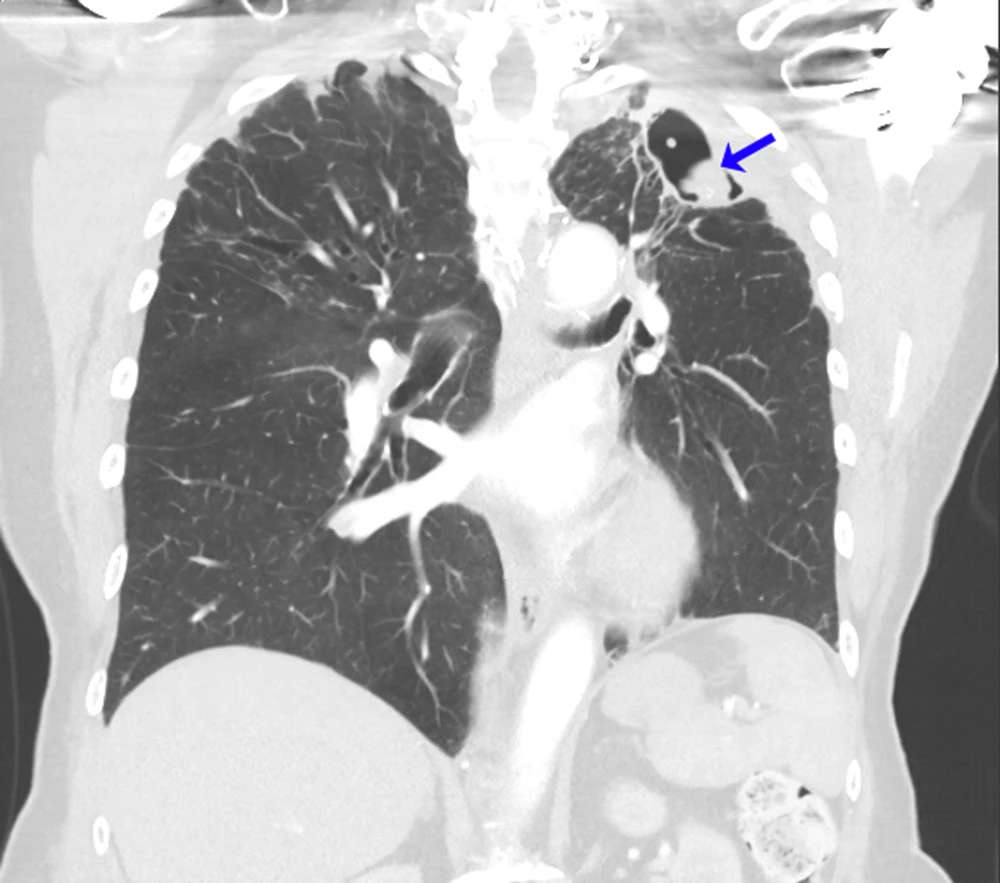

U do nấm Aspergillus.jpg

U phổi do nấm Aspergillus. Ảnh: Th.s, BS Paschalis Vergidis/MSD Manual